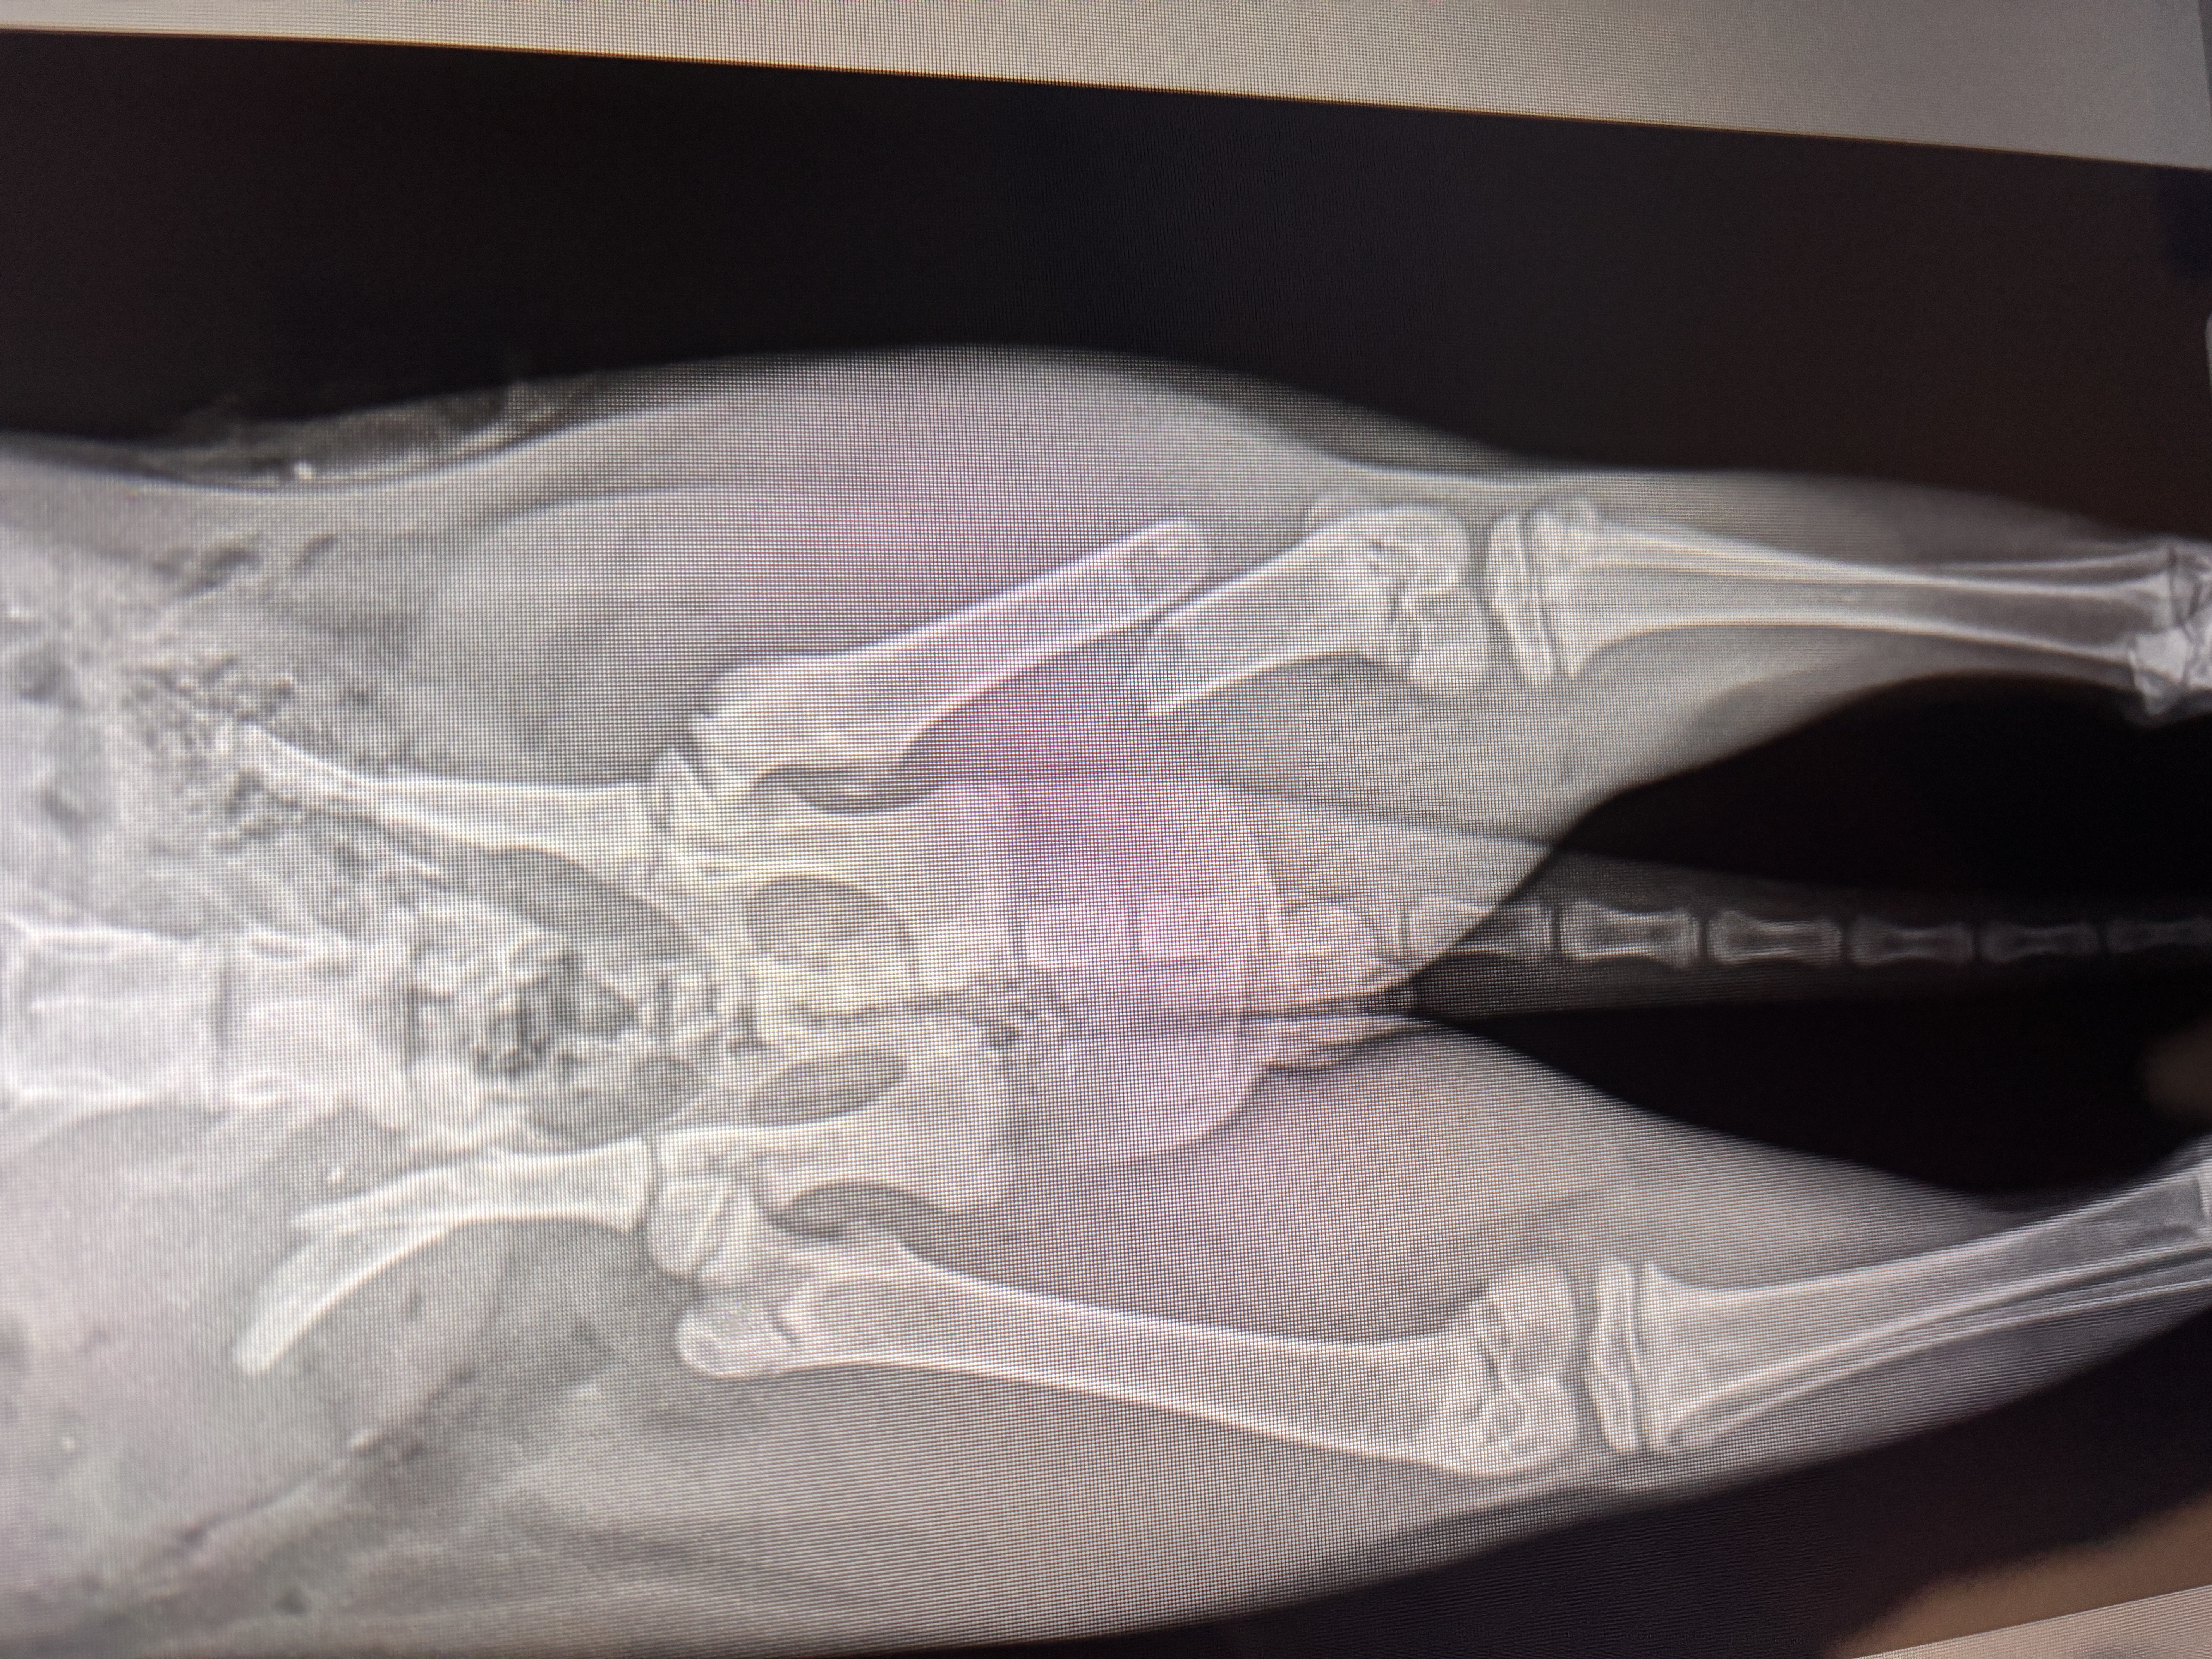

This is JoeJoe! He lives with his dad and both are considered homeless. The Canyon Animal Care Foundation was able to save his life while Joejoe was going through a serious life threatening condition of prostatitis and spinal disc inflammation. JoeJoe was so painful he was unable to eat, go to the bathroom and also unable to walk or use his hind limbs. We were so happy to report JoeJoe has now returned back to normal after his surgery, treatments and the care of his dad. THANK YOU for your donations. You make a difference in the lives of pets in northern Arizona. This means the world to their owners who do not have homes or resources to help their best friends.